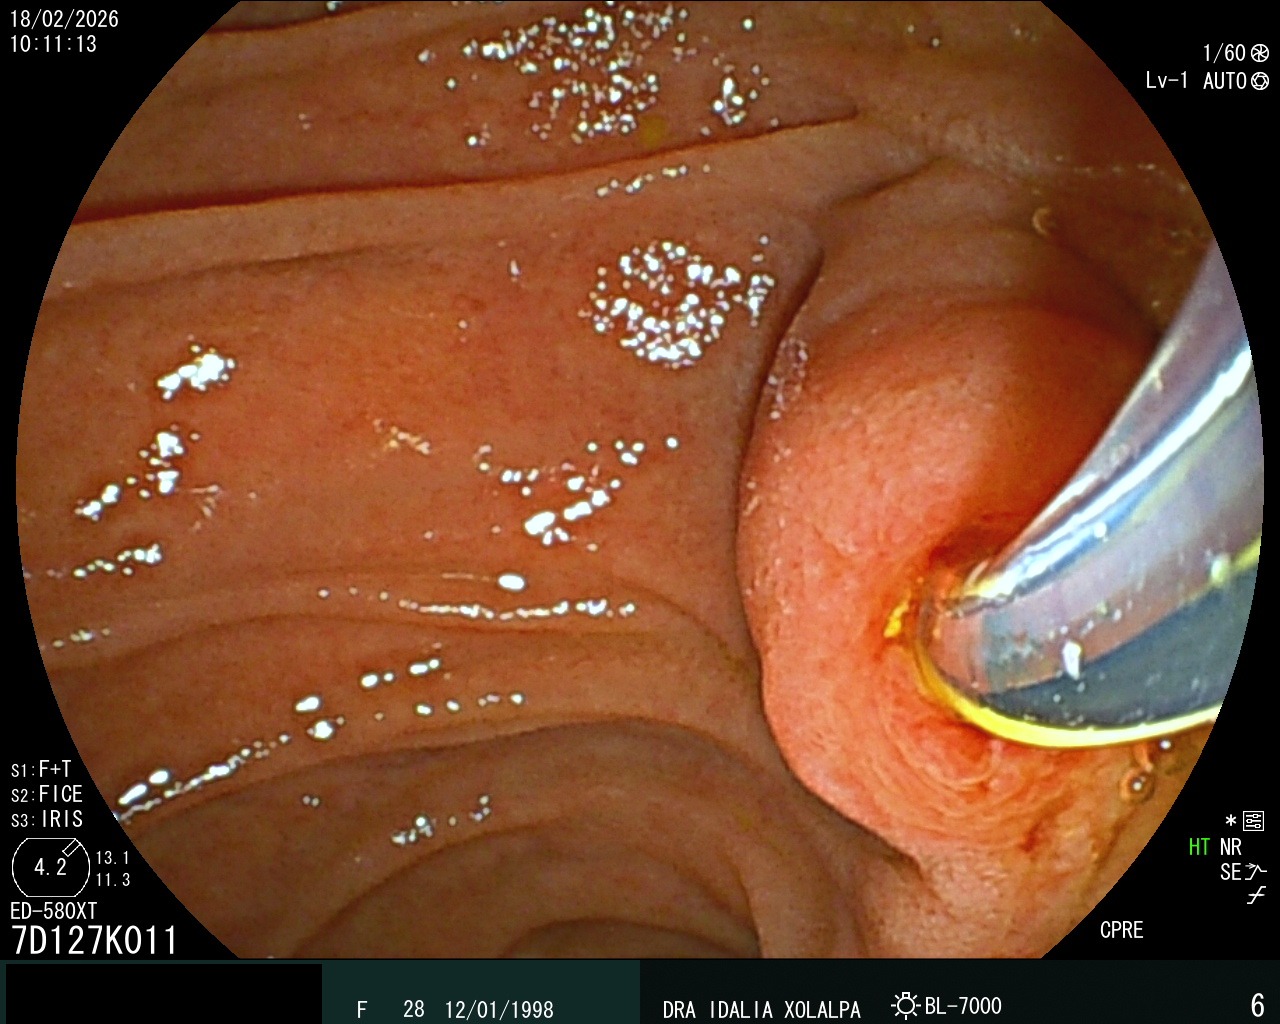

CPRE

Colangiopancreatografía Retrógrada Endoscópica